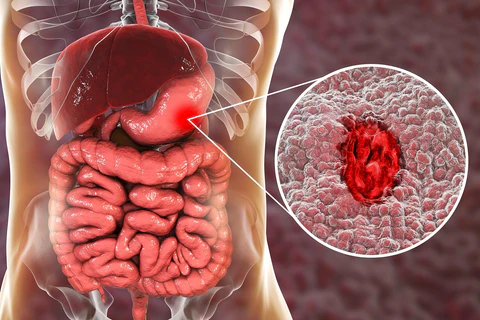

In addition to regulating fat accumulation in the stomach, Naturish™ PRO Vegan Natural Herbal Drops have other important benefits. For example, they can speed up metabolism, promote the absorption of nutrients in the body, and improve immune function.

Moreover, Naturish™ PRO Vegan Natural Herbal Drops can promote intestinal health, reduce intestinal inflammation, and improve overall digestive health. By restoring stomach health with Naturish™ drops, you can better control your diet, increase energy levels, reduce fatigue, and promote overall body health. If you are looking for a natural, effective, and safe way to improve your physical health, Naturish™ drops are a worthwhile choice to try.

Naturish™ Drops is a product developed by a research team led by Dr. Gilbert H. Mudge. It uses pure natural herbal ingredients and is designed to be easily absorbed by the human body. The product can effectively repair stomach tissue, restore normal gastrointestinal function, and improve gastric dissolution ability within 3 weeks. It can also eliminate excess fat regeneration, thus helping to restore your healthy body.